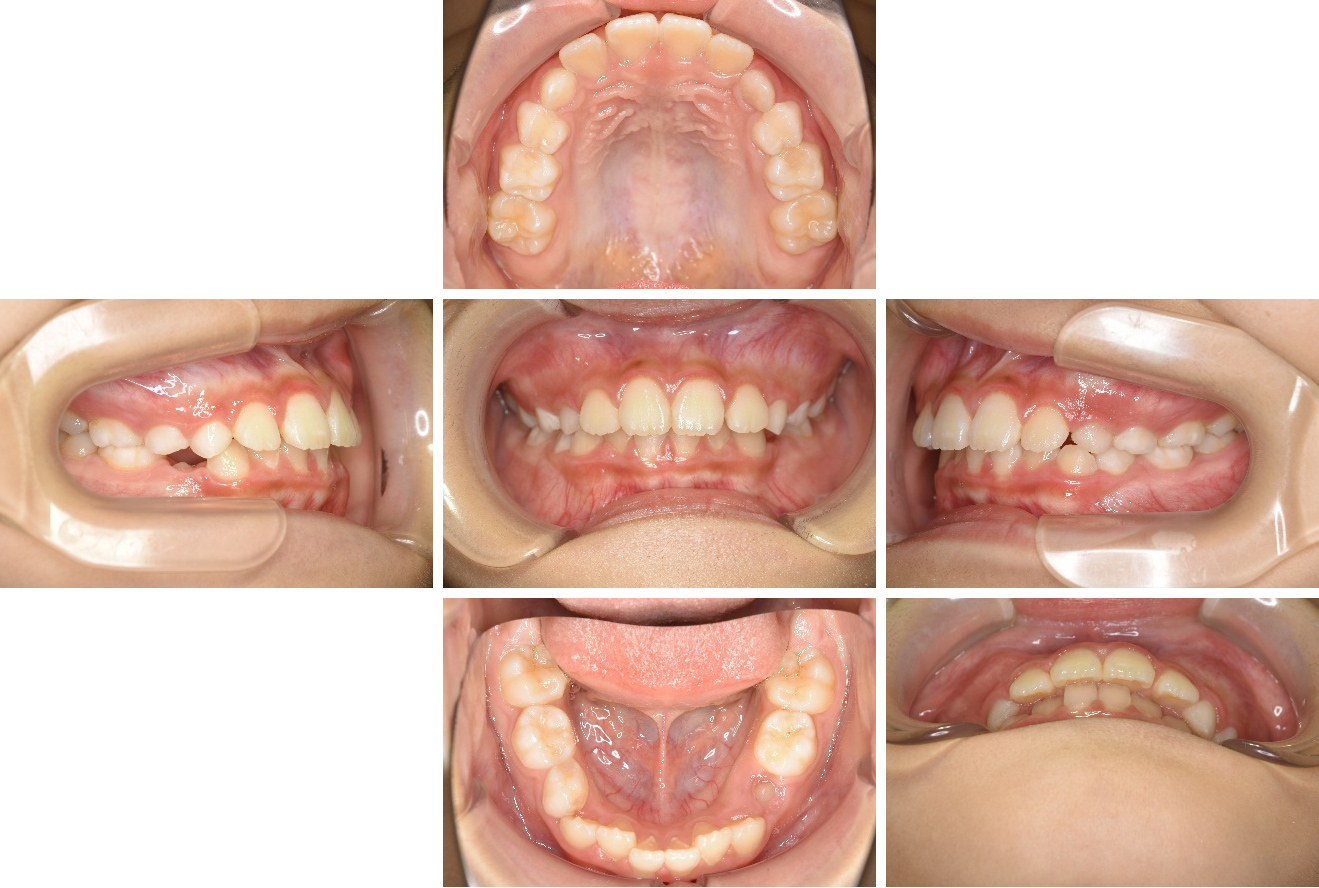

口角鈎という唇を引っ張る道具や、口腔内ミラーを使っていろいろな角度から6枚法で撮影します。

①咬んだ状態の正面

②咬んだ状態で上下の前後的な位置関係がわかる面

③咬んだ状態で左側

④咬んだ状態で右側

⑤口を開けた状態での上顎の咬合面(歯列)

⑥口を開けた状態での下顎の咬合面